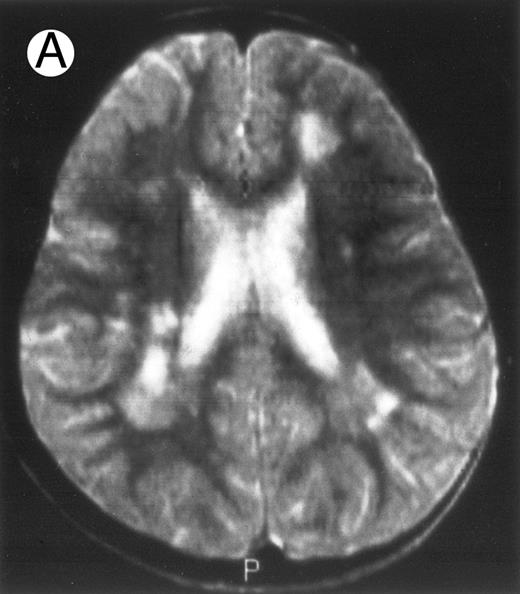

Among the nine children with initial neurological symptoms, seizures were the most frequent initial symptom in the youngest patients, whereas ataxia was found in the two oldest patients (46 and 58 months old, respectively) (Table 1). All nine patients had the same CSF abnormalities as patients with meningitis only. Eight of these nine patients had a neuroradiological study performed at the time of their first neurological symptoms (Table 1). The two most frequent lesions were focal necrosis with parenchymal volume loss and atrophy (Fig 2A and C) and white matter abnormalities (Fig 2B). Several small focal lesions with hypersignal at MR imaging that enhanced after administration of gadopentate dimeglumine (or contrast on CT scan) were also observed in two cases.

Three different aspects of brain imaging in HLH patients. (A) CT scan of a 3-month-old baby showing a large subdural effusion, several necrotic areas and hypodensities of the white matter. (B) Brain magnetic resonance of a 14-month-old boy showing large confluent areas of hypersignal in T2-weighted images. (C) Large symmetrical necrotic areas of cerebellar white matter in a 41/2-year-old girl (MRI).

Together, 19 patients had primary severe CNS disease progression or CNS relapse (Fig 1). Three of 19 had a CNS relapse characterized by meningitis only. Neurological symptoms occurred in 16 of these 19 patients (9 from the onset and 7 after the initial meningitis) (Fig 1). No clinical or neuroradiological difference was detected between the patients who developed neurological symptoms as the initial CNS manifestation or after initial meningitis (Table 1). The occurrence of these neurological manifestations marked a turning point in the evolution of the disease, as chemotherapy led to an improvement of the neurological symptoms in only three patients despite the use of intensive treatment by MTX IT. In these three patients, neurological sequelae persisted after the first symptoms and a relapse occurred within 3 to 10 months. Brain imaging was repeated during chemotherapy for four patients with progression of the CNS disease: in three patients, a severe brain atrophy developed (Fig 3A and B) and in the last patient who initially had contrast enhancement in cerebellar white matter, a cerebellum parenchymal loss was observed (Fig 2C). All of these 19 patients treated by chemotherapy only (n = 15) died during a last episode of coma and brain stem symptoms associated with a systemic hemophagocytic syndrome, 6 ± 6 months after the first neurological symptom (irrespective of the age at this first event). Four of these 19 patients were transplanted (one patient received an HLA-identical BMT, three an HLA-partially identical BMT). Median delay between diagnosis and BMT was 14 months (range, 2 to 20 months). All of these four patients died of BMT-related toxicity and/or disease progression.

Evolution of brain lesions during HLH. (A) MRI of a 41/2-year-old girl showing focal white matter hypersignal on T2-weighted images. (B) MRI of the same child 1 year later with an important atrophy of both the white matter and the cortices.